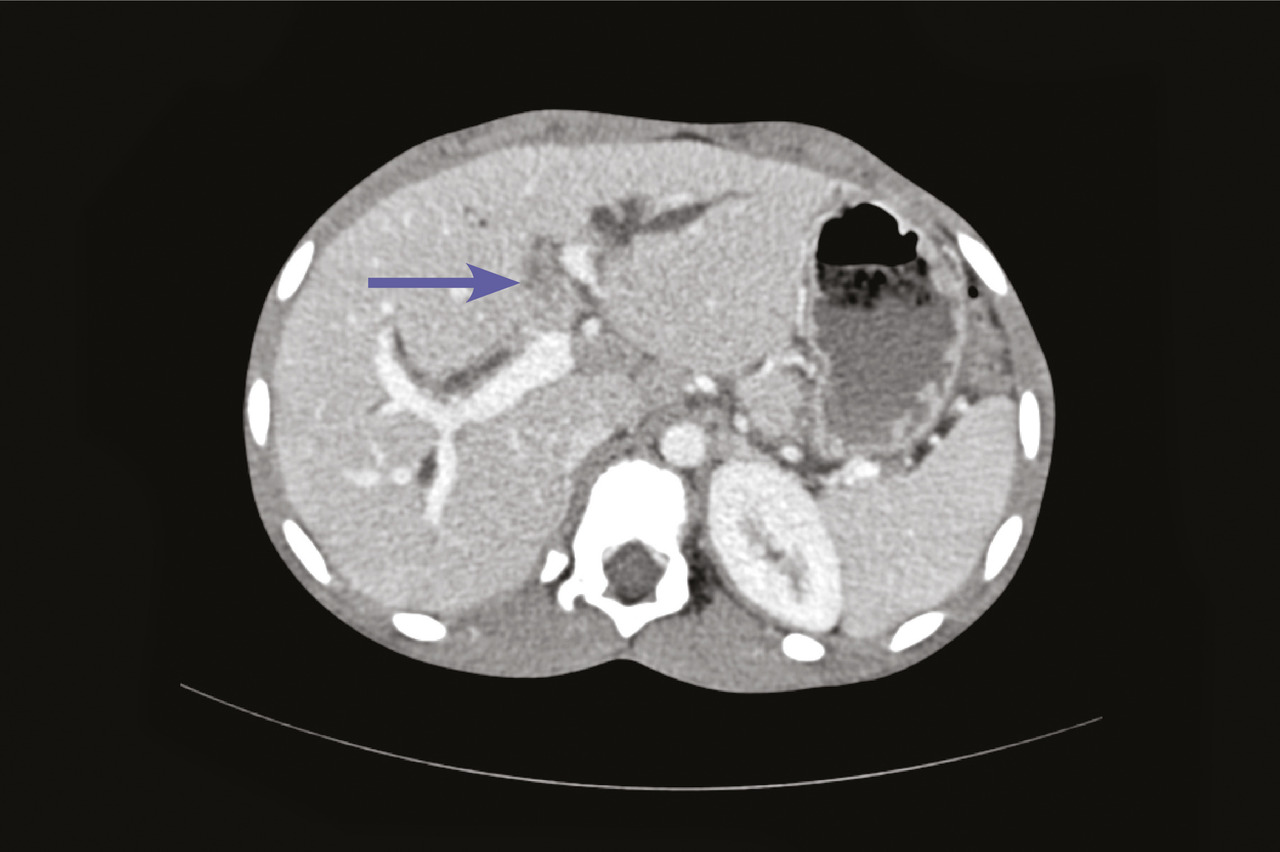

Ce garçon de 16 ans consultait pour des douleurs abdominales et des vomissements. En outre, il décrivait l’élimination de grands vers avec les selles. À l’examen clinique, il était légèrement dénutri. L’hémogramme montrait une hyperéosinophilie à 616/mm3. La tomodensitométrie abdominale montrait une image hyperdense au sein d’une dilatation des voies biliaires intrahépatiques (fig. 1 ). L’imagerie par résonance magnétique hépatique montrait un ascaris en hyposignal linéaire dans les voies biliaires intrahépatiques (fig. 2 ). Le patient était traité avec succès par albendazole.